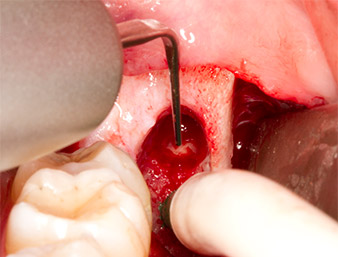

Mit einem Instrument für die parodontale Belagsentfernung (Piezomed P1) wurde anschließend der Parodontalspalt der Radix relicta minimal erweitert (Abb. 8).

Dasselbe aktivierte Instrument wurde in den Wurzelkanal eingeführt und lockerte das Fragment durch seine mikro-oszillierenden Vibrationen (Abb. 9, 10).

Piezomed P1

Abb. 9: Das Instrument Piezomed P1 wird vom Hersteller primär für die parodontale Belagsentfernung empfohlen, eignet sich aber auch für chirurgische Zwecke. Hier wird es nach minimaler Erweiterung des Parodontalspalts im Wurzelkanal platziert.

Abb. 10: Aufgrund seiner grazilen Form kann das Instrument in den Wurzelkanal eindringen und den Wurzelrest durch Mikro-Oszillation (Vibration) entfernen.

Anschließend ließ sich der etwa sechs Millimeter lange Wurzelrest in einem Stück mit dem P1-Aufsatz entfernen (Abb. 11).